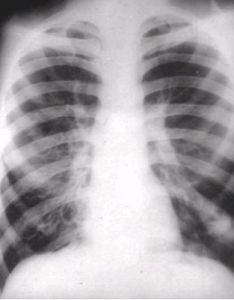

3.X線胸

可無異常(占10%)或肺紋理增多、增粗,排列紊亂。囊狀支氣管擴張在胸片上可見粗亂肺紋理中有多個不規則蜂窩狀(捲髮狀)陰影,或圓形、卵圓形透明區,甚至出現小液平,多見於肺底或肺門附近。柱狀支氣管擴張常表現為“軌道征”,即在增多紋理中出現2條平行的線狀陰影(中央透明的管狀影)。

4.X線檢查示肺紋理增多、增粗,排列紊亂,其中可見到捲髮狀陰影,並發感染出現小液平,CT典型表現為“軌道征”或“戒指征”或“葡萄征”。確診有賴於胸部HRCT。懷疑先天因素應作相關檢查,如血清Ig濃度測定、血清γ-球蛋白測定、胰腺功能檢查、鼻或支氣管黏膜活檢等。